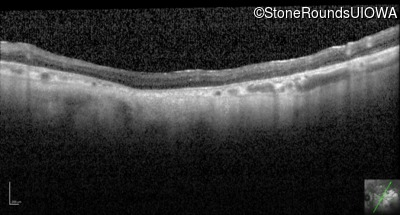

Optical Coherence Tomography - Left - 10/200 sc

Exemplar / OCT Stack